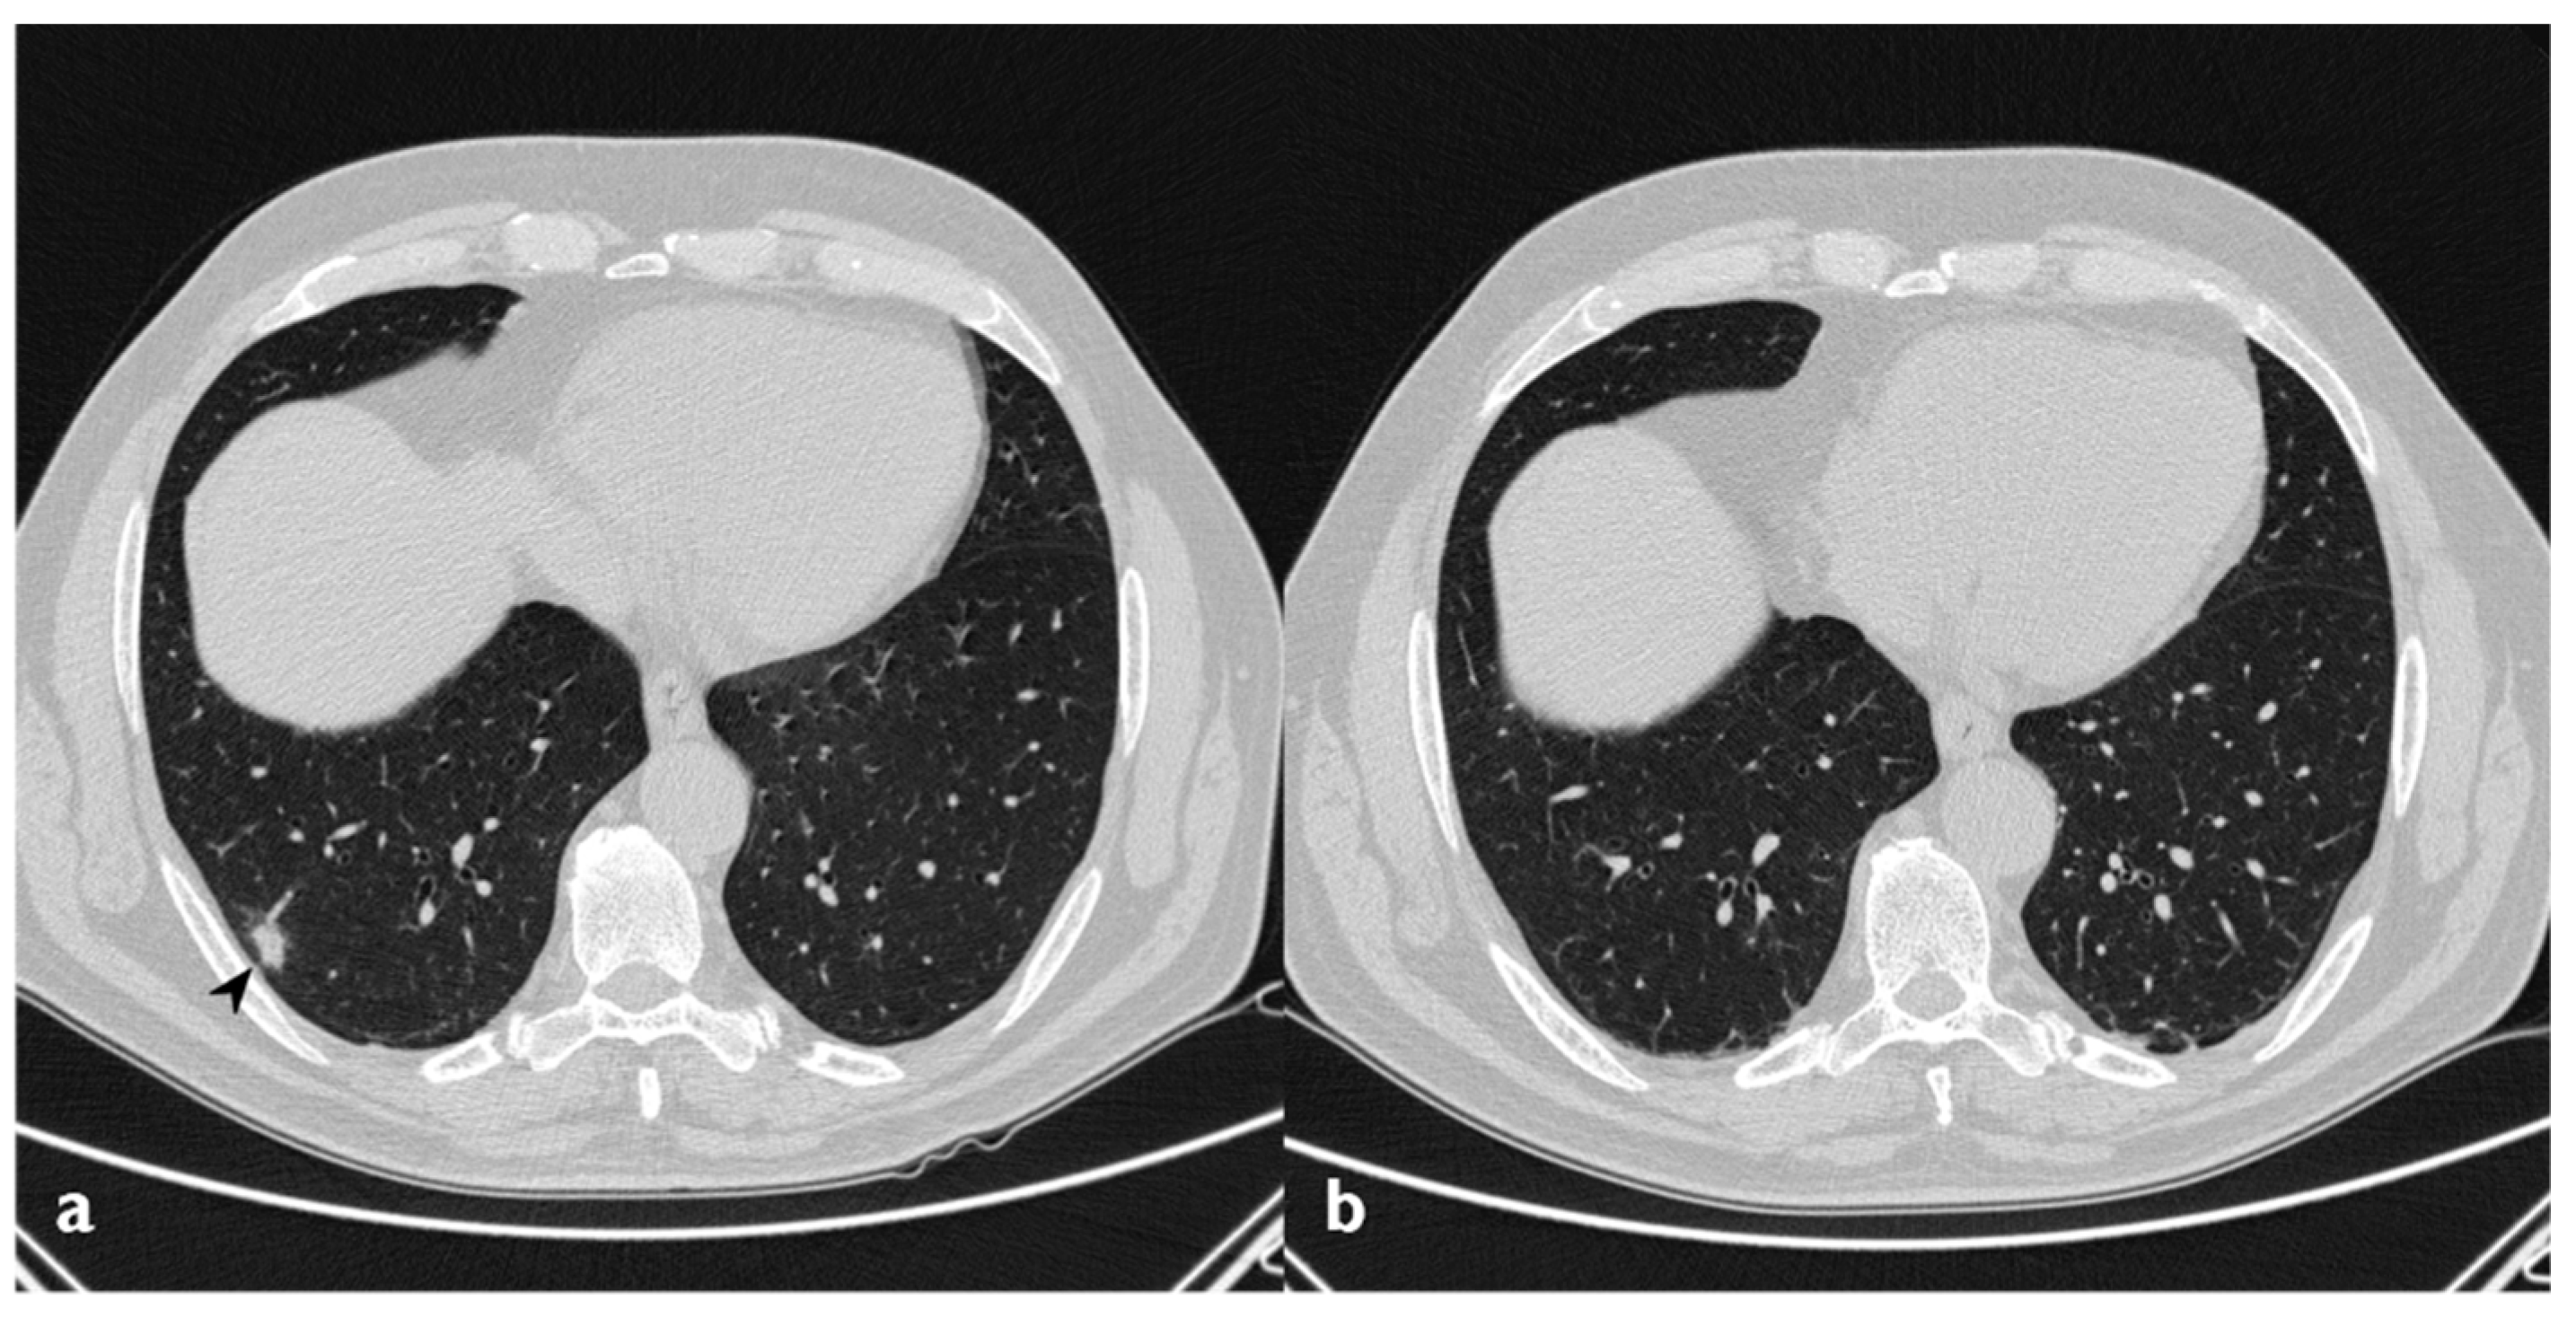

3.3. Ground Glass

Ground-glass opacities completely disappeared in nine out of 15 patients that have shown this pattern at baseline HRCT. In two patients, new ground-glass areas appeared where a previous consolidation was present, like residual components of the consolidations (Figure 10) (Table 6).

Figure 10. On the left (a): baseline HRCT; left parenchymal consolidations with air bronchogram sign in the context (arrowheads). On the right (b): HRCT after steroid treatment; new ground-glass areas (arrowheads) have appeared in the site of consolidations.